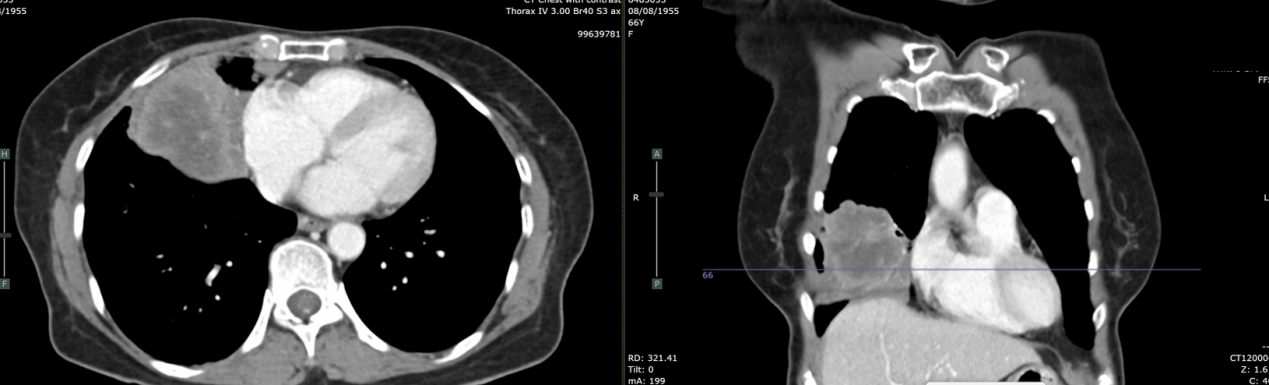

胸部增强CT(2021-12-21):右肺中叶及右肺下叶前基底段巨大软组织密度肿块,大小约6.8×6.3×8.5cm,边界不清;右肺上叶及下叶多发磨玻璃结节(最大1.0cm),考虑肺内转移;纵隔及双侧腋窝多发淋巴结融合肿大;左侧肾上腺见0.9×0.8cm低密度结节,可疑转移。气管及主支气管通畅,无胸腔积液,无骨破坏。

复查CT(2022-03-07):肿块增大至8.9cm,伴阻塞性肺炎,多发淋巴结最大达3.4cm。

复查CT(2022-04-05):肿块进展至9.4×7.7×7.1cm,侵犯右侧叶间裂、膈肌、胸壁及心包(脂肪间隙消失)。右肺多发纯磨玻璃结节0.4-1.0cm,考虑原位腺癌或非典型腺瘤样增生。纵隔淋巴结分布于右肺门、隆突下、右上及下气管旁区域,以及左上气管旁区域,最大3.3cm(隆突下)。